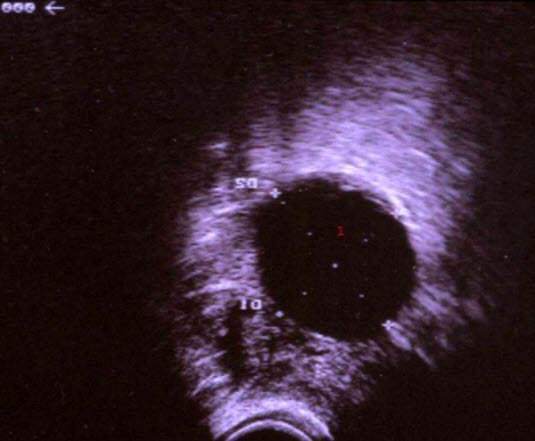

Enkamret, ekkofattig cyste

1. Cyste, væskefullt hulrom